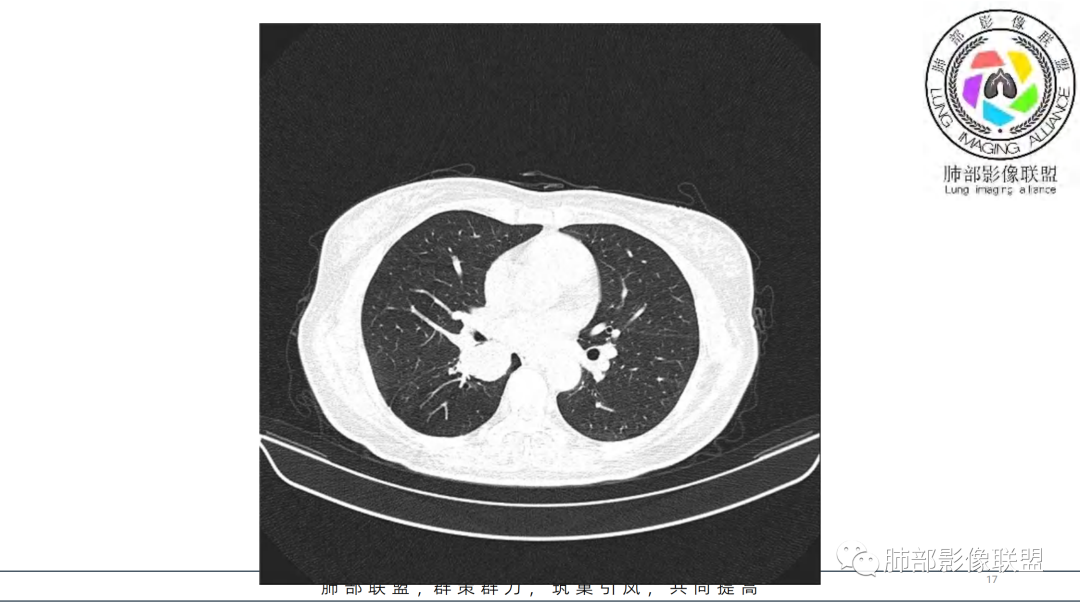

2.右肺下叶及中间段支气管后方类圆形块影,边界较清楚,未见分叶及毛刺,病灶部分突入支气管腔内(冰山一角),局部管腔狭窄,相应肺叶未见片影或体积变化。

3.块影密度均匀,未见液化坏死及钙化,渐进性强化,强化显著。

4.双肺门及纵隔未见增大淋巴结。未见胸腔积液。

中青年女性,支气管管腔内外肿块(“冰山征”),边界较清楚,强化显著,未见阻塞性肺不张,尽管未出现“类癌综合征”临床表现,仍然符合典型类癌影像学表现。